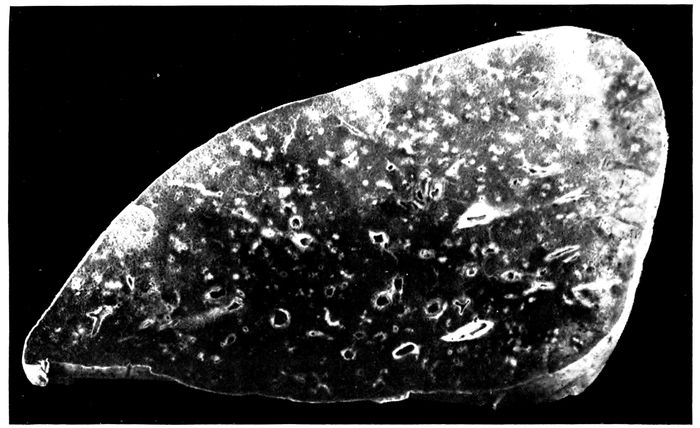

| 25. | Advanced bronchiectasis throughout lower left lobe | 258 |

| 26. | Unresolved bronchopneumonia with tubercle-like nodules of peribronchiolar consolidation best seen in lower lobe; bronchiectasis | 268 |

| 27. | Unresolved pneumonia with peribronchial formation of fibrous tissue; bronchiectasis | 270 |

| 28. | Unresolved pneumonia with bronchiectasis showing new formation of fibrous tissue about a greatly dilated bronchus of which the epithelial lining has been lost | 271 |